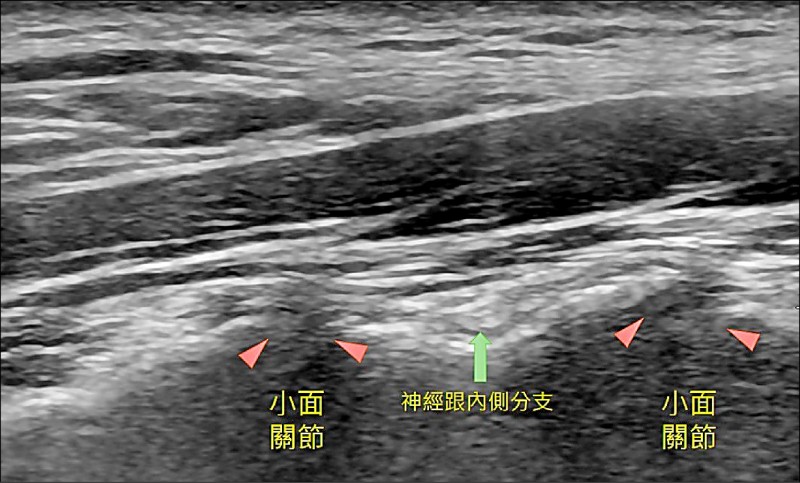

▲圖1:橘色三角形是小面關節處。(照片提供/徐幼鈞)

高老太太最近感到右後頸部疼痛合併右轉困難,右耳後方悶痛且會蔓延到後腦勺處,時不時有頭暈的感覺。她雖然已開始進行頸部熱療、電療與牽引,但好似沒有對到症頭。在評估過X光後,醫師在超音波輔助下發現右側第3-6節之間的小面關節有明顯骨刺和局部壓痛,枕大神經有腫脹。在施予高濃度葡萄糖水增生療法於小面關節處(圖1),以及枕大神經解套術後(圖2),頸部活動角度與頭痛的問題達到改善。